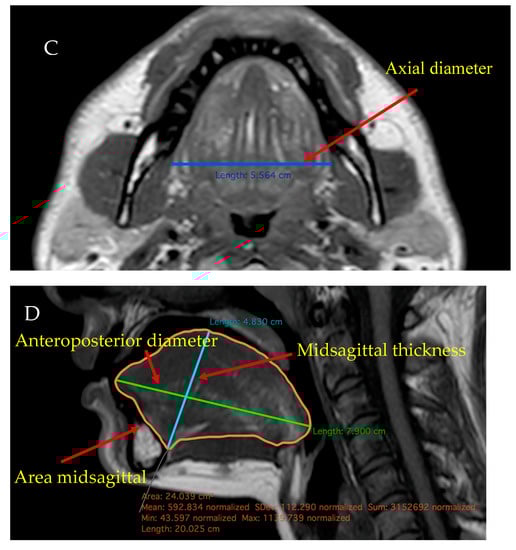

2.4. MRI

MRI measurements were carried out at the Medical Imaging Centre of Semmelweis University using a Philips Ingenia 1.5 T MRI device. MRI scans were conducted from the posterior nasal spine to the hyoid bone. As part of the neck MRI study, measurements of sagittal T2 TSE, STIR and T1 TSE, coronal T1 TSE (each with a slice thickness of 3.5 mm without gaps), and axial T2 SPIR, T1 TSE, and DWI (with a slice thickness of 3 mm with a gap of 1.5 mm) were performed. A Philips IntelliSpace Portal (Philips Healthcare, Best, The Netherlands) was used to analyse the scans and an experienced radiologist interpreted the results. The patients were examined in supine position and instructed to breathe normally through their noses.

The sagittal diameter of the tongue was measured in the anteroposterior directions, as the longest diameter between the apex and the base of the tongue. Tongue thicknesses were defined as the longest diameters between the origin of the genioglossus muscle and the surface of the tongue. Both calculations were based on T2 and T1 TSE weighted images.

The coronal and axial diameters were defined as the longest laterolateral diameters in the coronal or axial direction in coronal T1 TSE, axial T2 SPIR and T1 TSE scans. The midsagittal area (cm2) means the surface measured in the middle line of the sagittal axis, which was determined using the DICOM viewer software. The volume of the tongue was calculated using a semiautomatised analysis software (Philips IntelliSpace Portal Multi-Modality Viewer). The measurement was based on the calculation of the Region of Interest and volume rendering.

Tongue Fat% was defined as the ratio of the area on the midsagittal axis that shows the density of fat and the total surface of the tongue. In T1 weighted images, continuous adipose tissue in the tongue can be relatively well differentiated, and tongue Fat% was calculated using the fat area in the middle of the tongue using sagittal images and scaled to the midsagittal tongue area (Figure 2).

Figure 2.

(A,D) sagittal, (B) coronal, (C) axial T1 TSE MRI scans showing the anteroposterior, axial, coronal, sagittal, and midsagittal diameters, and also the calculation of Fat% (taken from our data).